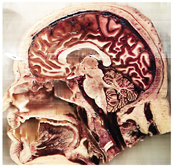

Table 2, Table 3, Table 4 and Table 5 present the results obtained through the multi-objective optimization image enhancement approach. Specifically, Table 2 and Table 3 show the results for natural images, while Table 4 and Table 5 display medical images. The tables are organized as follows: the first and second columns list the image names and their corresponding original, unenhanced versions. The third to fifth columns showcase the selected points from the Pareto front, representing the maximum contrast, knee point, and maximum detail, in that order. The final column illustrates the obtained Pareto front through the optimization process, with red, green, and orange points indicating the images that achieved maximum contrast, knee point, and maximum detail, respectively.

Table 4.

Medical image results—1.

Table 5.

Medical image results—2.

As observed in the results, the images extracted from the Pareto front significantly maximize contrast and detail compared to the original images. In all study cases, the original image is dominated by the solutions extracted from the fronts, demonstrating the approach’s effectiveness in improving visual quality. However, the differences among the three enhanced images for each problem require a more detailed analysis.

For medical images, there are instances where differences are more perceptible. For example, in the Medical3 image, the maximum contrast solution makes it difficult to visualize the internal details of the basophil (a white blood cell highlighted in the box), which could result in a less accurate interpretation. In contrast, the knee and maximum detail solutions provide a clearer view of the interior of the white blood cell. Similarly, in the Medical5 image, the maximum contrast solution highlights the hand and arm bone structures. However, the maximum detail image offers a more precise view of the internal structures within the bones (see the highlighted region), which is crucial for a more detailed evaluation. Another notable example is the Medical8 image, where the maximum detail solution offers a more detailed view of the internal structure of the eosinophil (another type of white blood cell). However, the maximum contrast image improves the visibility of red blood cells. As shown in the yellow box, this solution reveals a red blood cell that is nearly imperceptible in the other solutions. An interesting case is the Medical6 image, where only a few non-dominated solutions are present on the Pareto front. Despite the similarities among the preferred solutions, the nodules are much more perceptible in the enhanced images than in the original image, as observed in the highlighted region.